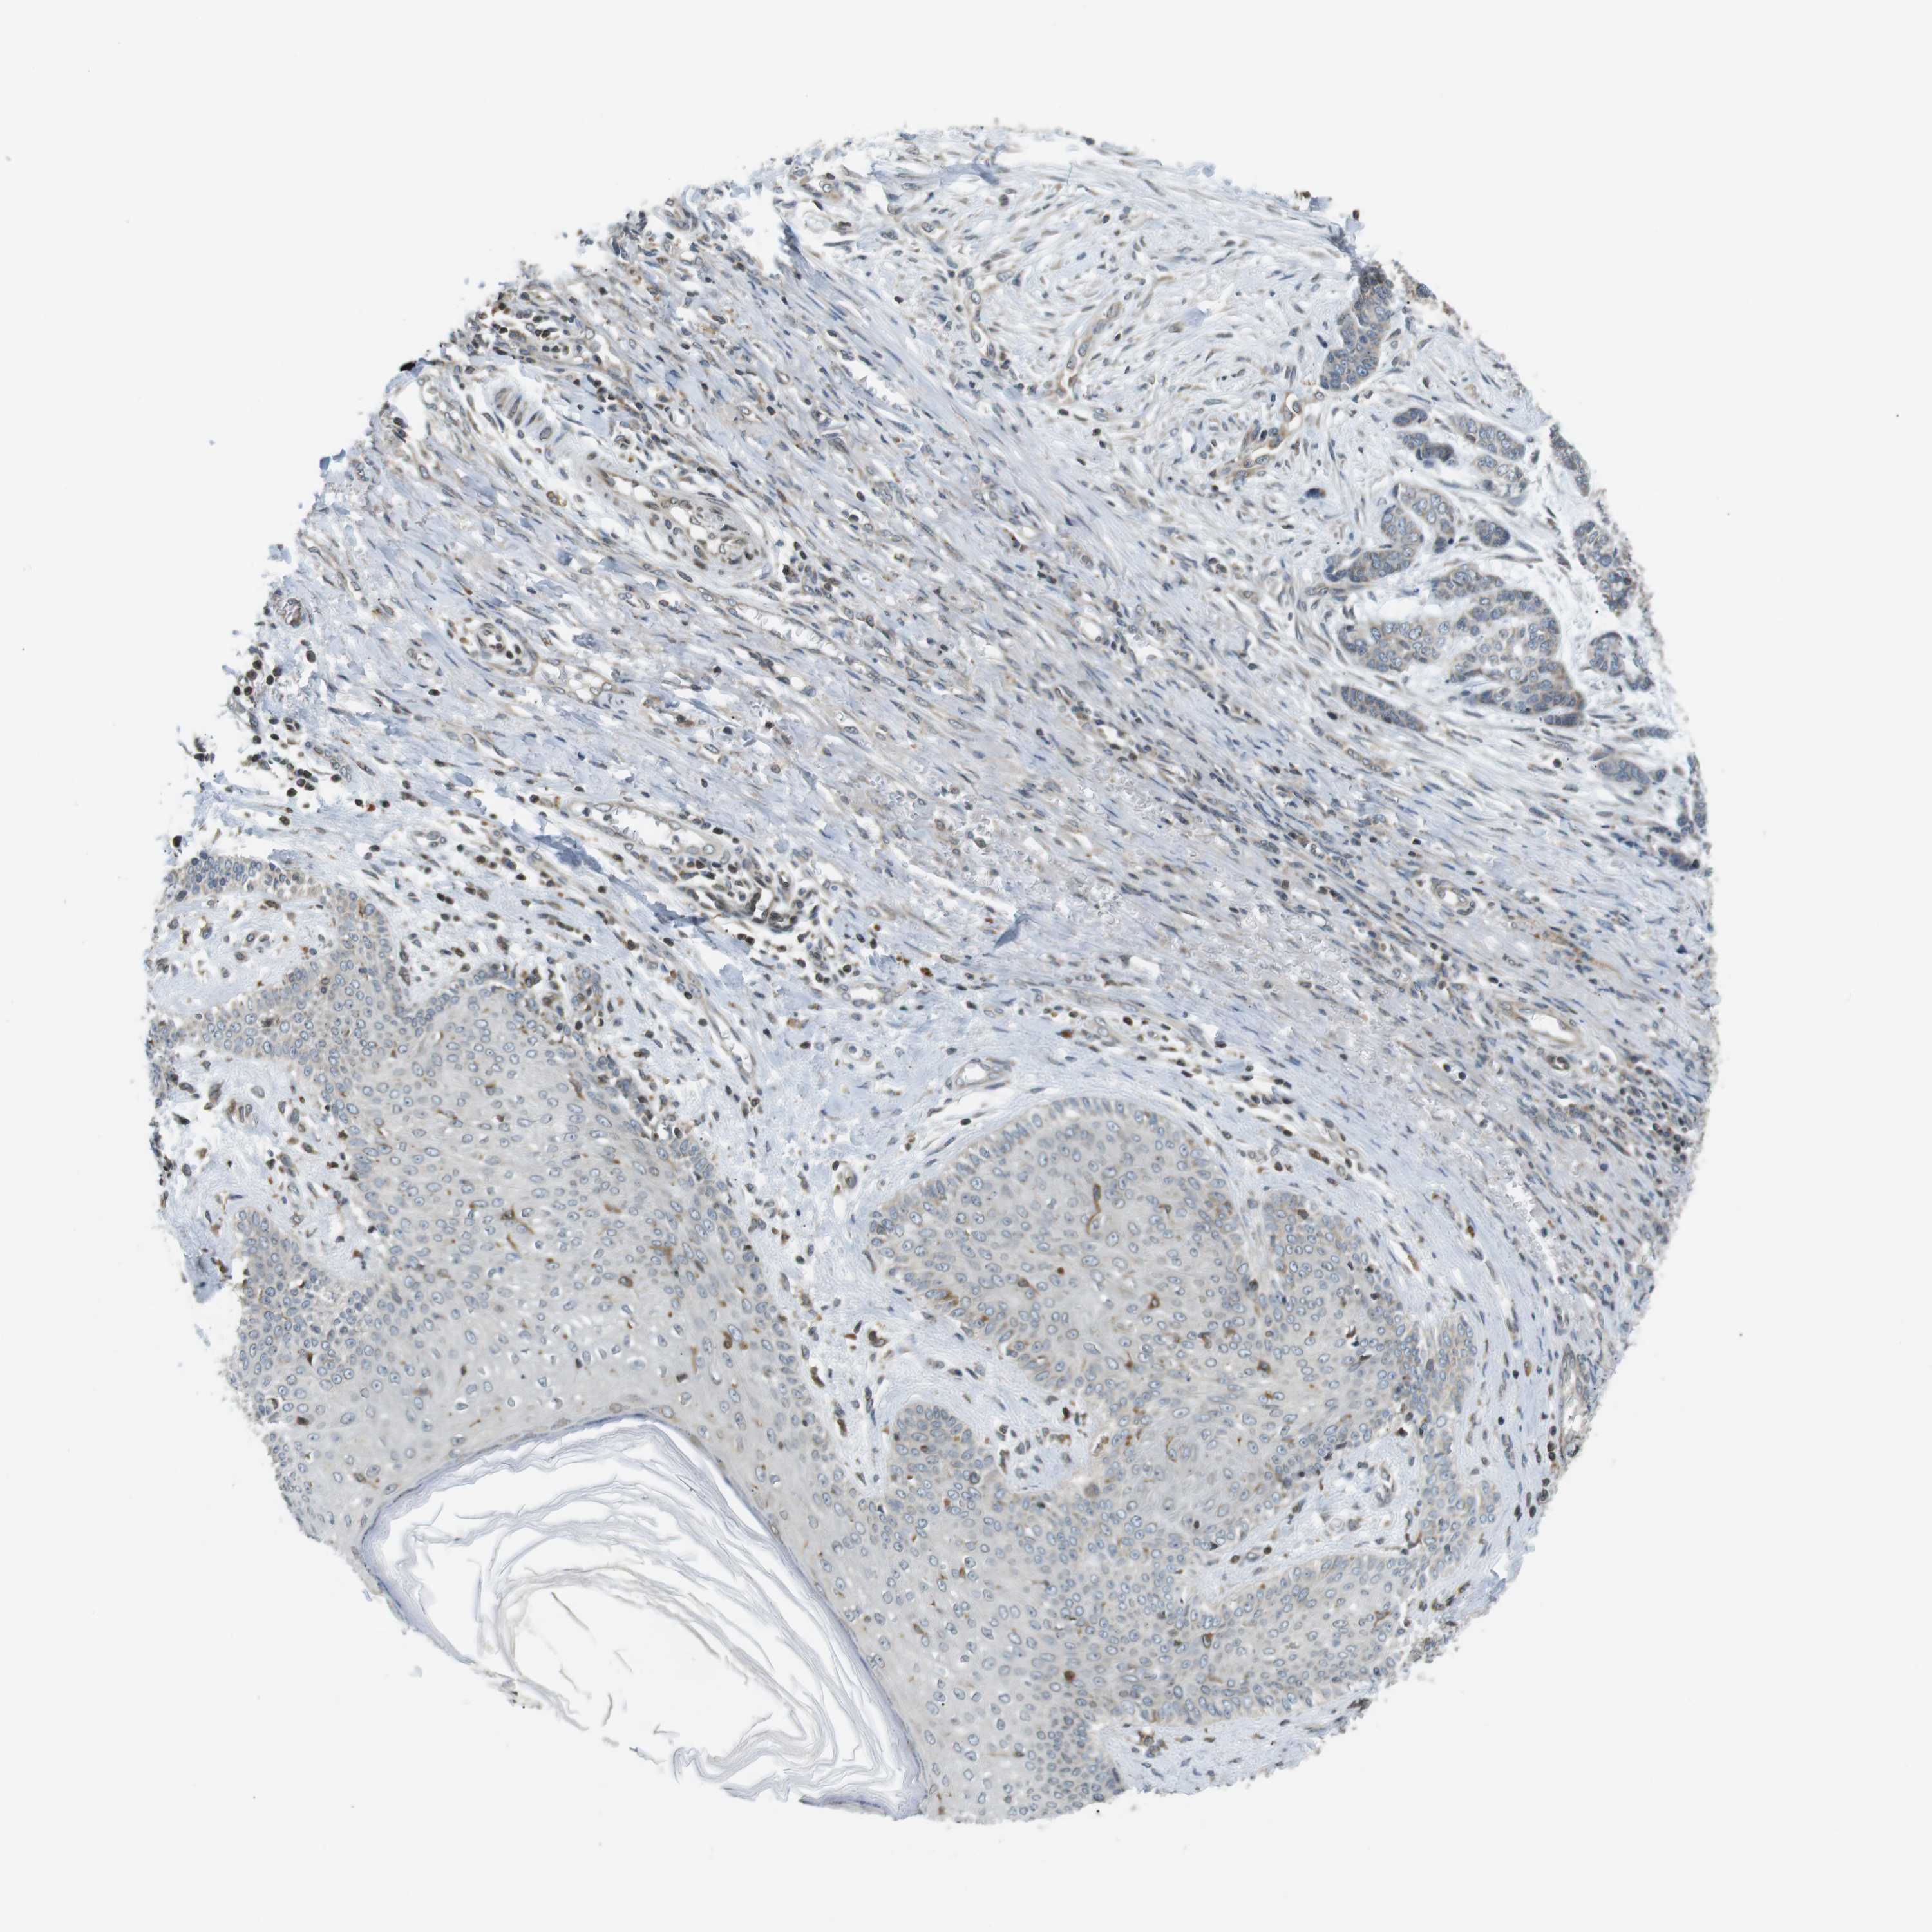

Basal cell and squamous cell cancer

SKIN CANCER - Protein expressioni

A mouse-over function shows sample information and annotation data. Click on an image to view it in a full screen mode. Samples can be filtered based on level of antibody staining by selecting one or several of the following categories: high, medium, low and not detected. The assay and annotation is described here.

Antibody stainingi

Antibody staining in the annotated cell types in the current human tissue is reported as not detected, low, medium, or high, based on conventional immunohistochemistry profiling in selected tissues. This score is based on the combination of the staining intensity and fraction of stained cells.

Each image is clickable and will lead to virtual microscopy that enables deeper exploration of all samples and also displays staining intensity scores, fraction scores and subcellular localization as well as patient and tissue information for each sample.

Antibody HPA000399

Antibody HPA015752

Staining

High

Medium

Low

Not detected

Intensity

Strong

Moderate

Weak

Negative

Quantity

>75%

75%-25%

<25%

None

Location

Nuclear

Cytoplasmic/membranous

Cytoplasmic/membranous,nuclear

Squamous cell carcinoma, NOS

Squamous cell carcinoma, metastatic, NOS

Basal cell carcinoma

Squamous cell carcinoma in situ, NOS

Adnexal tumor, benign